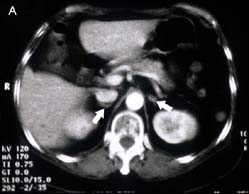

ต่อมหมวกไต เป็นอวัยวะคู่ซึ่งอยู่บริเวณส่วนบนของไตทั้งสองข้าง ต่อมหมวกไตข้างขวาจะอยู่เหนือกว่าและอยู่ด้านข้าง lateral ต่อไตมากกว่าข้างซ้ายซึ่งจะอยู่หลังกว่า splenic vessels และเห็นในระดับของ pancreatic tail ดังรูปที่10

รูปที่ 10 ภาพ CT และ MRI ของต่อมหมวกไตปกติ

รูป A. ภาพ CT ลูกศรแสดงต่อมหมวกไตปกติข้างขวาและข้างซ้าย ( ระนาบ coronal ) รูป B. ภาพ MRI T1 WI ของต่อมหมวกไตปกติข้างขวาและข้างซ้าย (ลูกศร) เป็นระนาบตัดขวาง

รูปร่างของต่อมหมวกไตอาจเปลี่ยนแปลงตามระดับของ cross sectional imaging ข้างขวามักเป็นรูป linear หรือ inverted V หรือ K configuration ข้างซ้ายอาจเป็น linear, inverted V, triangular, inverted Y หรือรูปดาว เป็นต้น ความกว้างของขาประมาณ 2-3 มิลลิเมตร และไม่ควรเกิน 5 มิลลิเมตร(11) ส่วนใหญ่ของ cortisol-producing adrenal masses จะใหญ่กว่า 2 เซนติเมตร ซึ่งเห็นได้ชัดใน CT หรือ MRI การตรวจโดย CT มักจะเป็นทางเลือกแรกซึ่งสามารถวินิจฉัยได้แม่นยำ เนื่องจากผู้ป่วยเหล่านี้มักอ้วนมีไขมันล้อมรอบต่อมหมวกไตมากทำให้เห็นได้ชัดเจน ใช้เวลาตรวจสั้นและราคาถูกกว่า MRI